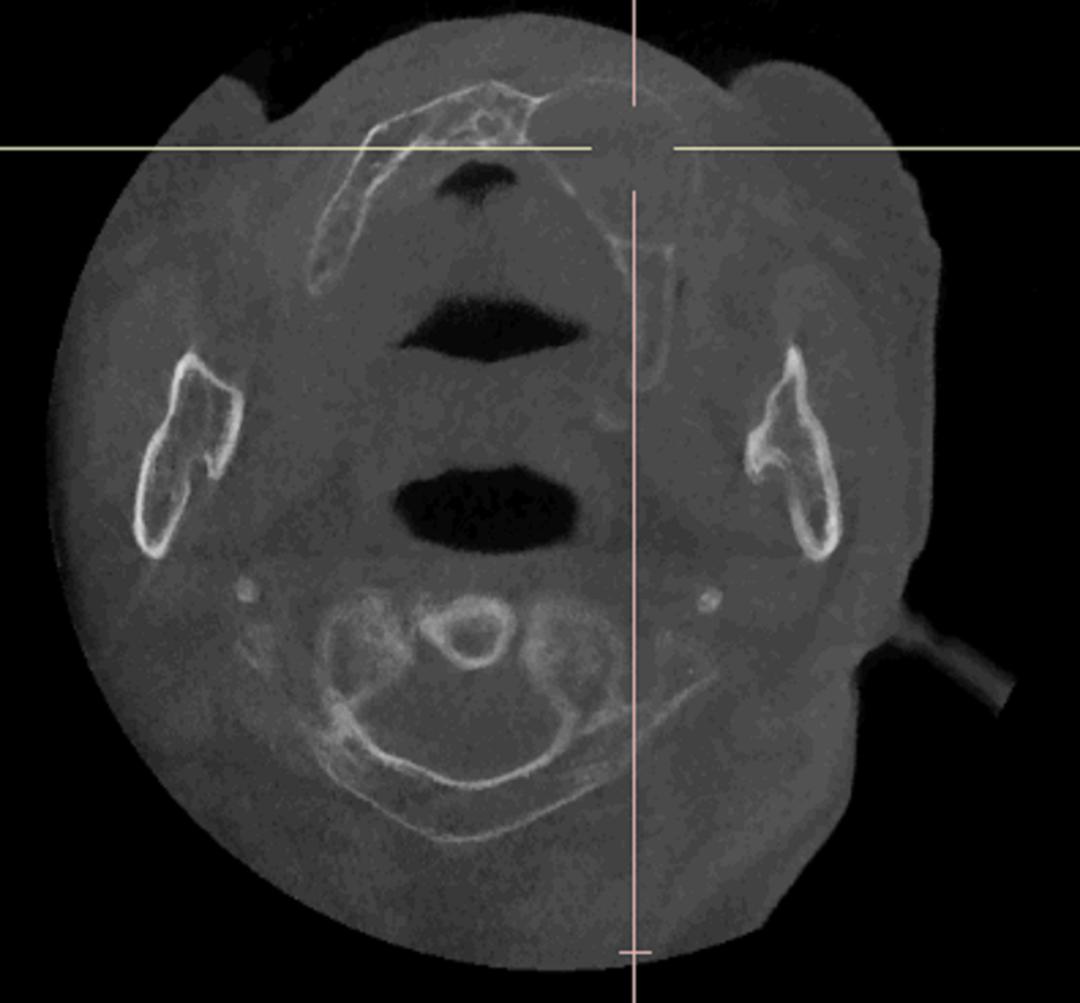

医生通过CBCT检查发现,这个囊肿边界清晰,且与鼻腔底部关系密切。“这个囊肿很可能是导致您反复肿痛的根源。它虽然属于良性病变,但因为位置特殊,已经压迫到了周围骨骼,导致骨质变薄,需要尽快手术处理。”医生指着片子耐心解释道。

考虑到张老先生年事已高,且有高血压,医院组织了多学科会诊,进行了全面的术前评估。在确保安全的前提下,为他实施了全麻下的“左上颌骨病损切除术”。手术顺利完整切除了肿物。术后复查时,张老先生高兴地对医生说:“这下好了,戴上假牙总算不疼也不肿了!”术后病理报告证实了术前的怀疑:牙源性角化囊肿。